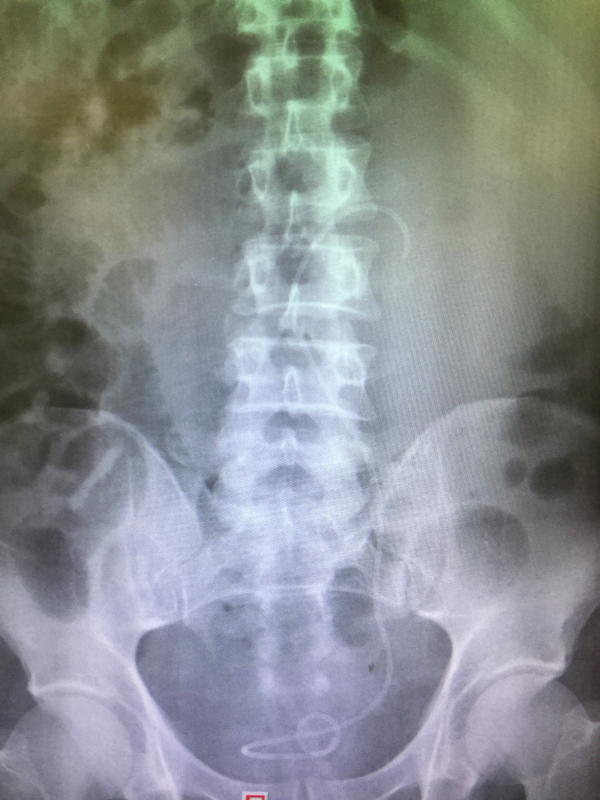

在老刘住院期间,泌尿外科的医生和护士众志成城,细心监护,一共请血液科、肿瘤科等科室专家进行了16次会诊,为他进行15次输血,2次抢救……虽然过程艰辛且曲折,但最终,泌尿外科的医护人员和老刘一起战胜了病魔,获得了成功,术后的老刘精神状态变得很好,白细胞值接近正常值,术后复查X光片显示结石被清理得很干净!12月10日,老刘顺利康复出院。出院当天,老刘一家还执意要和梁泰生主任合影留念以表感谢。

结石已被清理干净